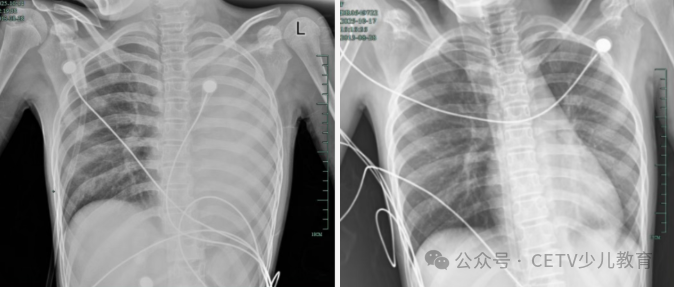

治疗前后影响对比,左肺从“白肺”到正常状态。

呼吸急促、胸闷胸痛,体温38.5℃,只能靠 5L/min 的面罩吸氧维持血氧,胸片显示左肺已完全呈 “白肺” 改变,肺部炎症进展迅猛。